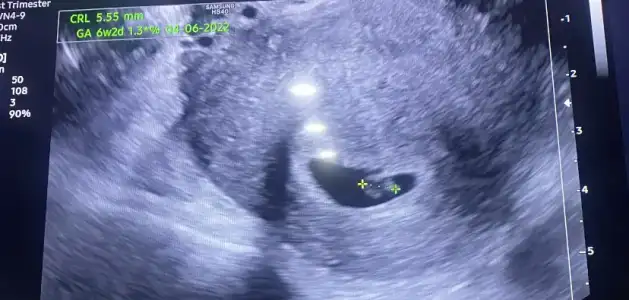

ben kontrolden çıktım, ikili test için kan alındı, sonuçları iki gün içinde çıkar denildi, detaylı kontrolde de ensesini vs ölçtüler, her şey yolundaymış, kan sonucu da çıkınca arayacaklar

fotolarda görüldüğü üzere parmak emenler kulübünden, aç kaldı yavrucak

%90 erkek dedi